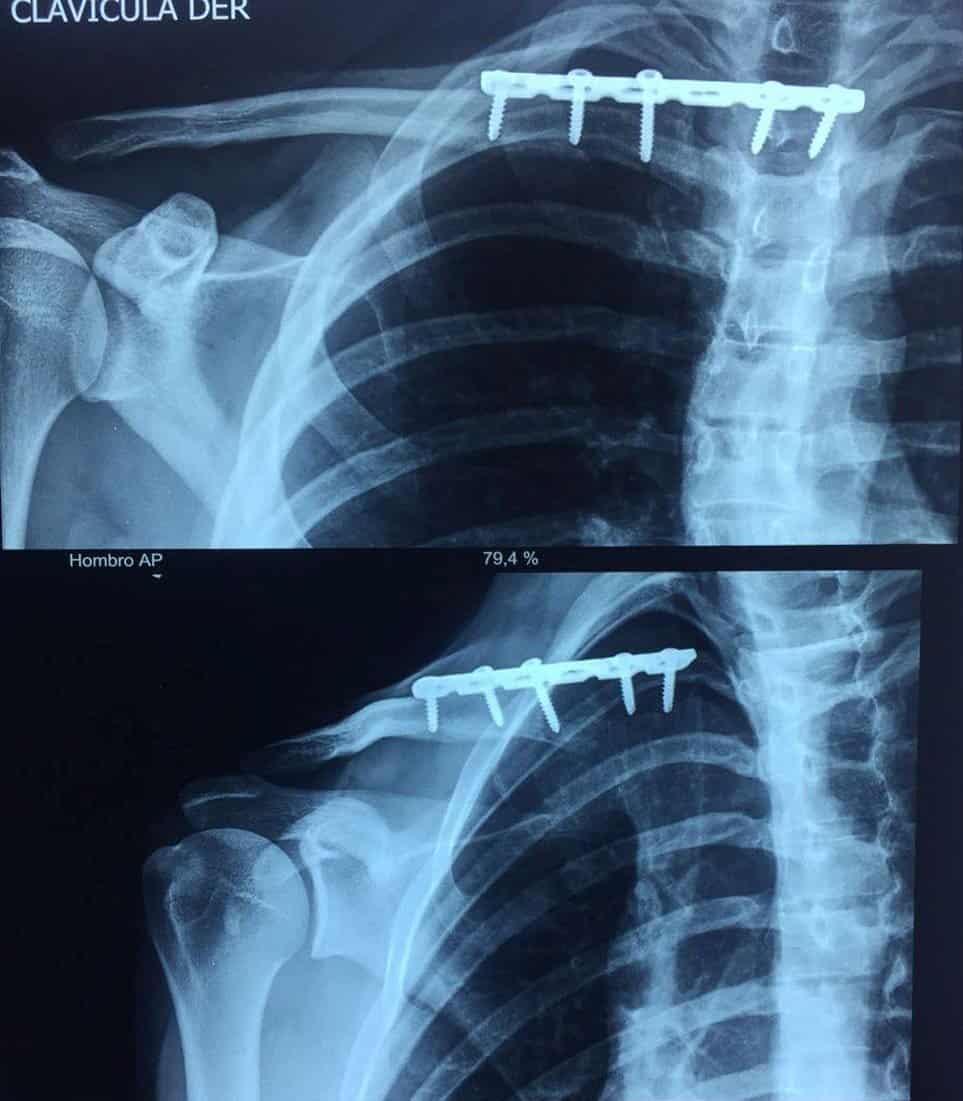

Trật khớp ức đòn

» Thông tin: Nam giới – 23 tuổi.

» Lâm sàng: Chấn thương vai phải.

# Trật khớp ức-đòn phải ra sau.